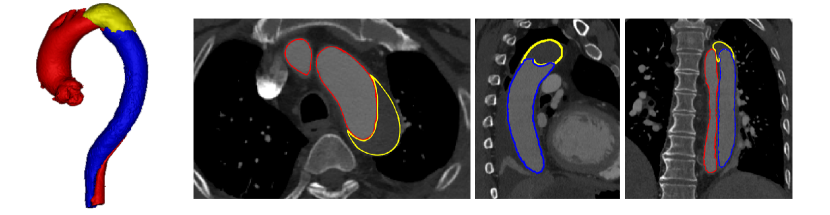

Refer to caption

Figure 1: Visualization of TBAD in a 3D model including FLT (yellow), TL (red), and FL (blue), and the corresponding CTA image with axial, coronal, and sagittal views.